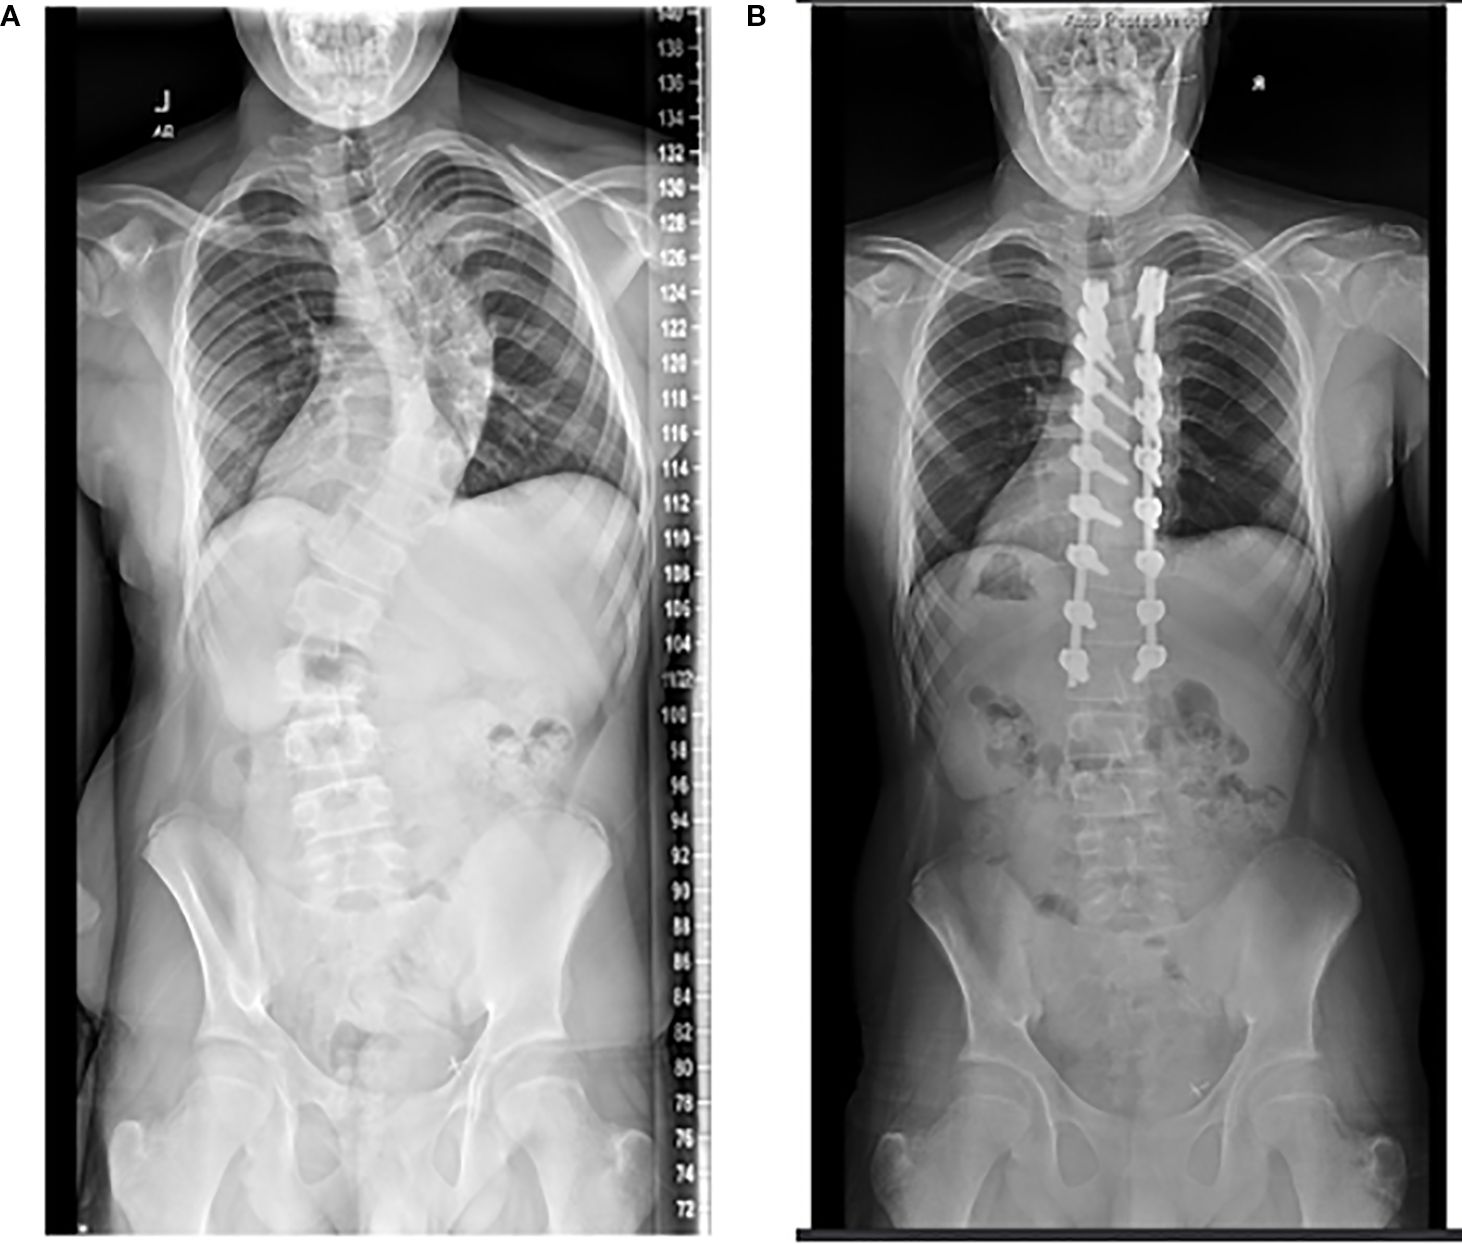

Spine fusion surgery is usually considered when the angle of deformity is greater than 50 degrees in the e plane. Once the deformity is that large, even if the patient is skeletally mature, it is expected for the curve to continue to progress by 1–2 degrees annually. During surgery, an extensive posterior approach to the spine is performed and two rods are secured to either side of the vertebrae using pedicle screws and/or hooks. As the rods are placed, the typical “S” shaped deformity is corrected in the coronal plane and kyphosis and/or lordosis is re-introduced in the sagittal plane (Figure 4).

Figure 3. Radiographs of the same patient, who at 17 years of age underwent posterior spine fusion for thoracic-level scoliosis (A, B). Of note, he received a renal transplant at age 16.